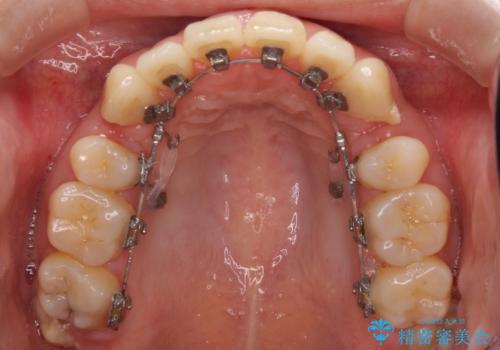

- リンガルブラケット

上顎の前から4番目の歯を両側抜歯して、上下裏側の装置で前歯を引っ込める計画としました。